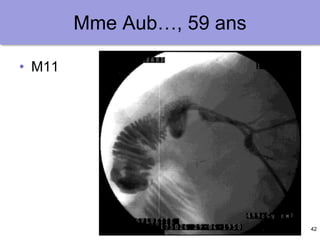

Mme Aub…, 59 ans

• M10

42

• M11